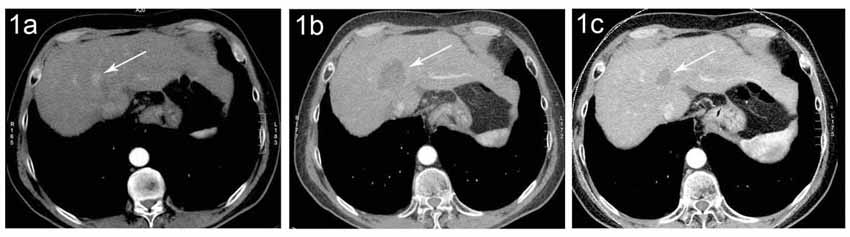

Abbildung:

Abbildung A zeigt eine CT Angiographie der rechten Nierenarterie bei einer jungen Patientin mit schlecht einstellbarem Bluthochdruck. Die CTA zeigt deutlich eine hochgradige Abgangsstenose der rechten Nierenarterie (Pfeil). Anhand dieser CT Angiographie wurde die Entscheidung zur PTA und Stentimplantation getroffen, und die Behandlung wurde geplant.

Abbildung B zeigt die Angiographie unmittelbar vor der Stentimplantation, welche den CT-Befund bestätigt (Pfeil).

Abbildung C zeigt die Kontrollangiographie nach Stentimplantation (Pfeil) mit hervorragendem Ergebnis.